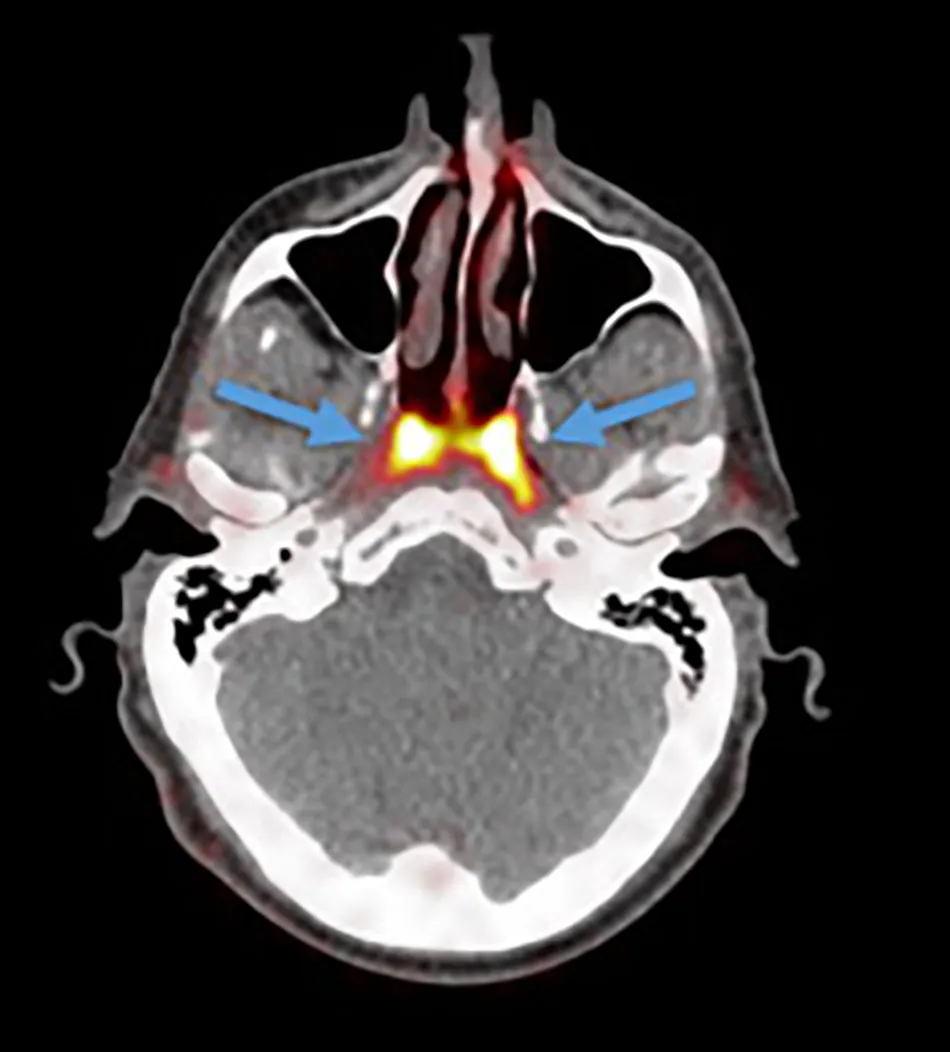

ନେଦରଲ୍ୟାଣ୍ଡର ବୈଜ୍ଞାନିକମାନେ ଏକ ନୂଆ କ୍ୟାନ୍ସର ସ୍କେନ୍ ଯାଞ୍ଚ କରୁଥିବା ବେଳେ ଗଳାରେ ଏକ ନୂଆ ଅଙ୍ଗ ବିଷୟରେ ଜାଣିବାକୁ ପାଇଥିଲେ। ଗବେଷଣାରୁ ଜଣାପଡ଼ିଲା ଯେ ମଣିଷ ଗଳାର ଉପରିଭାଗରେ ଗ୍ରନ୍ଥୀଗୁଡ଼ିକର ଏକ ଗ୍ରୁପ ରହିଛି। ବୈଜ୍ଞାନିକମାନେ ଏହି ଗ୍ରନ୍ଥୀର ନାମ Tubarial salivary glands ରଖିବା ସହିତ ଏହା ନାକର ଲୁବ୍ରିକେସନ୍ରେ ସାହାଯ୍ୟ କରିଥାଏ ବୋଲି ବୈଜ୍ଞାନିକମାନେ କହିଛନ୍ତି।

Radiotherapy and Oncology ଜର୍ନାଲରେ ପ୍ରକାଶିତ ଏକ ରିପୋର୍ଟ ଅନୁସାରେ, ରେଡିଏସନ୍ ଚିକିତ୍ସା ସମୟରେ ଯଦି ଏହି ଗ୍ରନ୍ଥୀଗୁଡ଼ିକ ଉପରେ କୌଣସି ପ୍ରଭାବ ନ ପଡ଼େ ତେବେ ଏହା ମଣିଷ ପାଇଁ ଉପକାରୀ ହେବ। ନେଦରଲ୍ୟାଣ୍ଡର ଏମ୍ସଟର୍ଡସର କ୍ୟାନ୍ସର ଇନଷ୍ଟିଚ୍ୟୁଟ୍ର ବୈଜ୍ଞାନିକ ପ୍ରୋଷ୍ଟେଟ୍ କ୍ୟାନ୍ସର ଯାଞ୍ଚ ପାଇଁ ପ୍ରସ୍ତୁତ କରାଯାଇଥିବା PSMA PET-CT ନାମକ ସ୍କାନ୍ର ପରୀକ୍ଷଣ କରୁଥିବା ସମୟରେ ରେଡିୟେକ୍ଟିଭଭ ଟ୍ରେସରକୁ ରୋଗୀର ସରିର ଇଞ୍ଜେକ୍ଟ କରାଯାଇଥିଲା ରେଡିୟେକ୍ଟିଭଭ ଟ୍ରେସର ପାଇଁ ମଣିଷ ଶରୀରେ ଥିବା ନୂଆ ଅଙ୍ଗ ବିଷୟରେ ଜଣାପଡ଼ିଥିଲା।/odishatv-khabar/media/post_attachments/aajtak/images/photo_gallery/202010/new-organ_020212.jpg)

ଗଳାର ଉପରିଭାଗରେ ଥିବା ଏହି ଗ୍ରନ୍ଥୀଗୁଡ଼ିକର ଲମ୍ବ ୧.୫ ଇଞ୍ଚ ରହିଛି। ଏହି ନୂତନ ଗ୍ରନ୍ଥୀଗୁଡ଼ିକ salivary glands ଭଳି। ୧୦୦ ଲୋକଙ୍କ ଉପରେ ହୋଇଥିବା ରିସର୍ଚ ସମୟରେ ପ୍ରାୟ ୧୦୦ ଲୋକଙ୍କଠାରେ ହିଁ ଏହି ଗ୍ରନ୍ଥୀ ଥିବା ଜଣାପଡ଼ିଥିଲା।